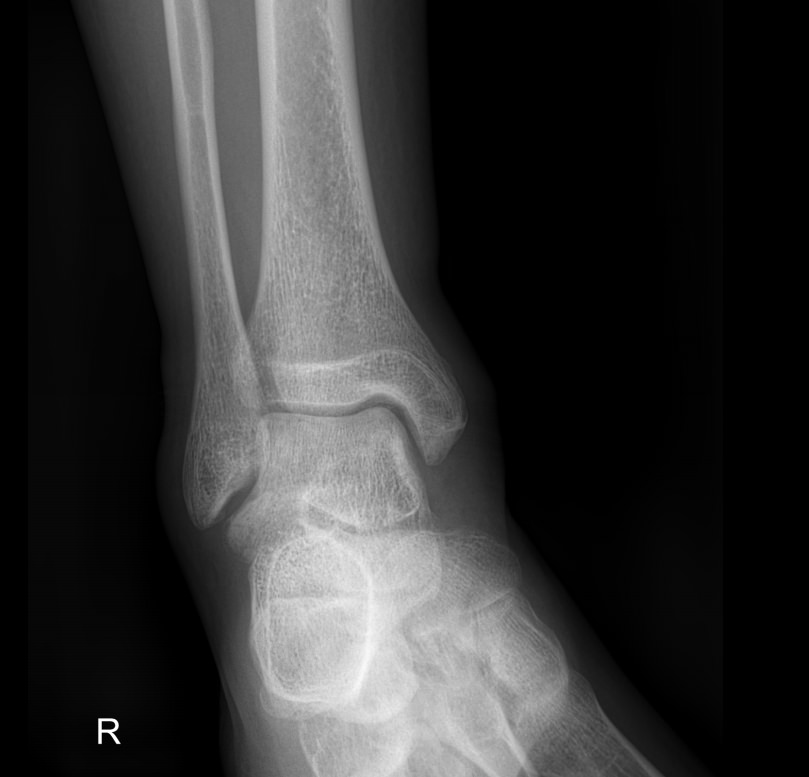

Голеностопные суставы отличаются сложным строением, в позволяющим стопе вращаться, сгибаться и разгибаться почти на 90о. Благодаря этому тело свободно перемещается в пространстве, меняет свое положение, поднимает собственный вес и дополнительный груз. Травмы голеностопных суставов встречаются также часто, как и хронические заболевания.

В качестве скринингового, а зачастую и единственного метода диагностики голеностопных суставов обычно используют рентген. Его вполне достаточно для визуализации внутреннего строения сустава и патологических изменений в нем. А цифровая нагрузка цифрового оборудования последнего поколения  несет минимум излучения и позволяет безопасно делать несколько снимков подряд.

Обследование обоих суставов с помощью рентгена помогает подтвердить диагноз, сравнить проявления на разных ногах, установить стадию заболевания, выбрать тактику лечения и определить его эффективность при следующих патологиях:

• Переломы и вывихи;

• Врожденные аномалии;

• Онкология;

• Дегенеративно-дистрофические заболевания.

• Изменения, произошедшие в костной ткани элементов суставов ― разрежение, некроз, озлокачествление, склерозирование;

• Нарушение четкости контуров костных образований;

• Перелом, его местоположение, смещение отломков;

• Состояние суставных щелей ― сужение, расширение, скопление жидкости, обызвествление капсулы;

• Конгруэнтность суставных поверхностей или вывих;

• Состояние мягких тканей ― отеки, инородные тела.